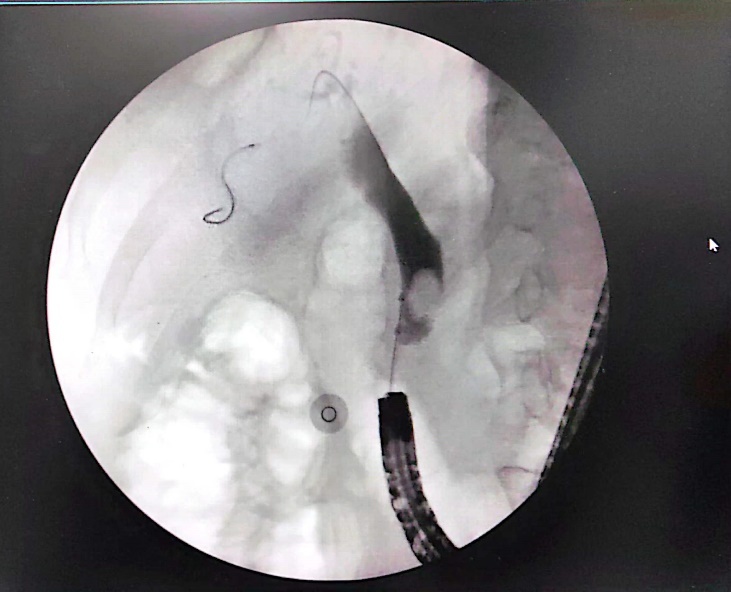

通过与家属充分沟通及积极的术前准备,熊光苏主任医师及张俊杰主治医师在内镜诊治中心陆蕊护士的娴熟配合下,通过运用肠镜进镜至输入袢,在多个肠腔腔道间反复尝试及寻找,最终找到了十二指肠乳头,经十二指肠乳头插管、球囊扩张后及碎石后,成功取出大量胆管结石,手术过程非常顺利。术后患者炎症及胆红素指标均恢复正常,标志着消化道改建术后ERCP术的圆满成功。

X线造影后表现